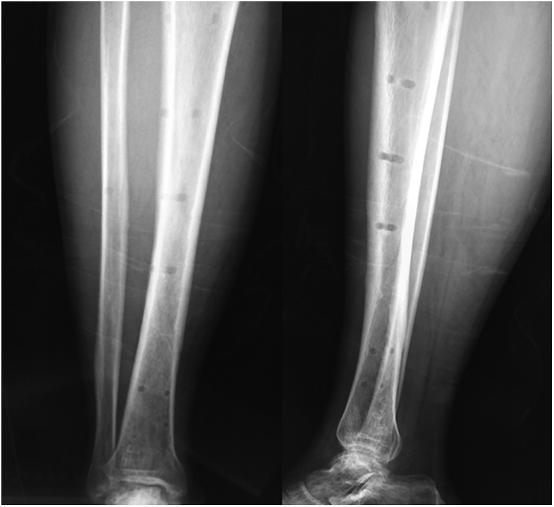

In this non-control prospective study, 28 patients with distal tibial fractures were included and underwent one-stage external fixation by using locking plate. There were 21 males and 7 females, with a mean age of 43 years (19-63). According to AO/OTA fracture classification, there were 9 cases of Type A1, 9 of Type A2, 10 of Type A3 fractures. There were 21 close and 7 open fractures. The locking plate was placed on the anteromedial aspect of the tibia with 4-5 bicortical screws inserted in both distal met- aphysis and diaphysis. The radiographic and clinic results were evaluated.

All patients were followed up for the average of 16 months (ranging from 12 to 21 months). The average surgery duration was 38 (25-60) minutes. The mean time to fracture healing were 14.6 ± 2.67, 17.5 ± 3.66, and 18.4 ± 3.37 (p < 0.05) weeks in type A1, A2, and A3 fractures respectively. By the end of the follow-ups, the mean AOFAS score were 96.11 ± 2.32, 92.67 ± 1.80 and 92.00 ± 2.06 (p > 0.05) in type A1, A2, and A3 fractures respectively. None of nonunion, deep infection, or breakage of screw or plate were observed.

Distal tibial fracture was the ideal indication for external fixation using locking plate. The external plating is characterized by ease of performance, less invasive, fewer soft tissue impingement, improved cosmesis, and convenient for removal.